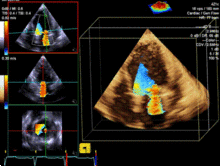

正常超声心动图

正常超声心动图,超声心动图正常值

超声心动图

超声心动图图片

超声心动图切面

二维超声心动图